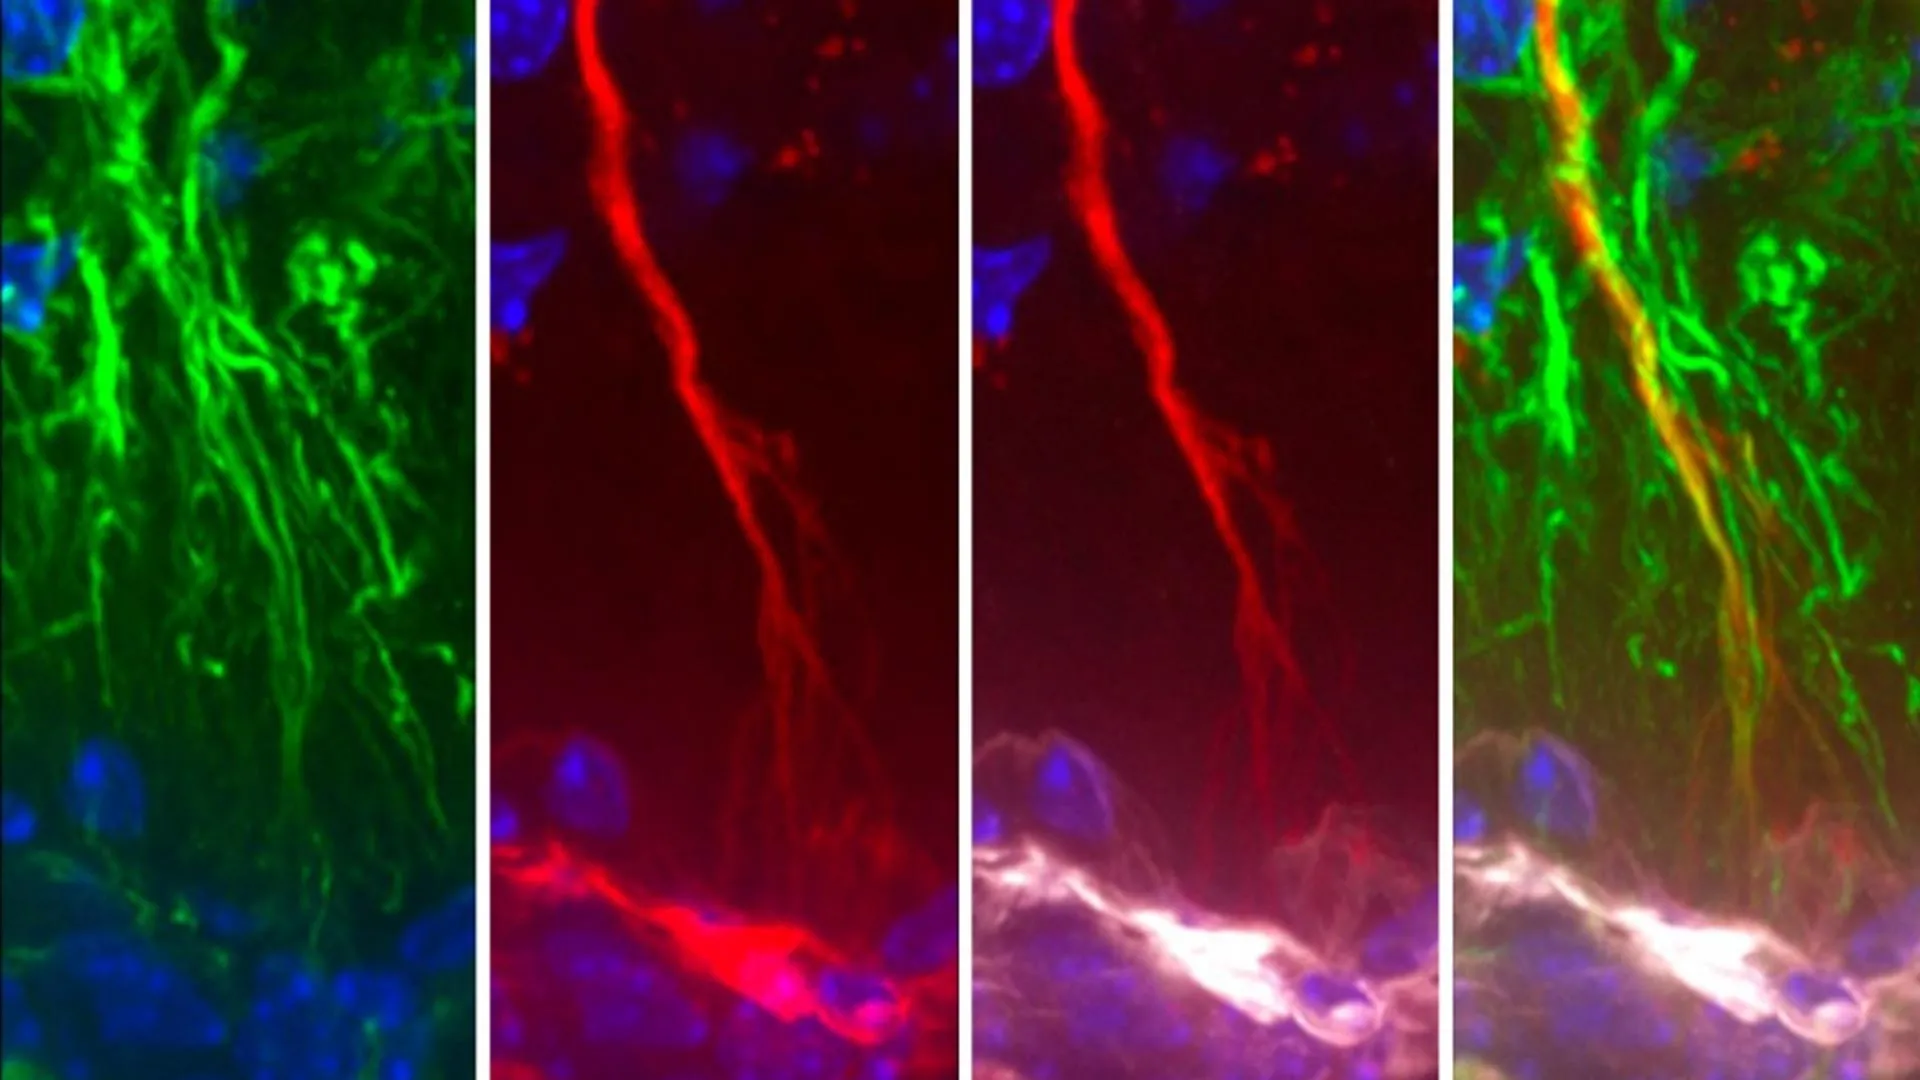

To understand the context of tanycytes’ newly revealed function, it is essential to define their anatomical location and known physiological roles. Tanycytes are not neurons; rather, they are glial cells, a category of non-neuronal cells that provide essential support and protection to neurons. They are predominantly situated in the lining of the third ventricle, a fluid-filled cavity within the brain that is part of the ventricular system. Historically, scientific literature has primarily associated tanycytes with the crucial task of facilitating the exchange of metabolic signals between the bloodstream and the cerebrospinal fluid (CSF). The CSF itself is a clear, colorless fluid that bathes and cushions the brain and spinal cord, playing a vital role in nutrient supply, waste removal, and maintaining the delicate internal equilibrium of the central nervous system, a state known as homeostasis.

The pivotal contribution of the current study lies in its detailed exploration of how tanycytes actively participate in the elimination of detrimental molecules, such as misfolded tau proteins, thereby contributing to the overall health of the brain. The research meticulously demonstrated that these specialized cells possess a remarkable capacity to transport toxic substances, including aggregated tau, from the CSF into the systemic circulation. Once in the bloodstream, these waste products can then be efficiently processed and cleared from the body by peripheral organs. The study’s critical insight is that when this sophisticated transport mechanism mediated by tanycytes malfunctions or becomes compromised, the accumulation of toxic tau within the brain is an inevitable consequence.

The experimental evidence supporting this conclusion was compelling. Researchers observed in both rodent models and isolated human cell cultures that tanycytes were indeed instrumental in the clearance of tau. Furthermore, a particularly striking finding emerged from the analysis of brain tissue obtained from individuals diagnosed with Alzheimer’s disease. These analyses revealed structural abnormalities within the tanycytes and significant alterations in their gene expression patterns, specifically in genes associated with their proposed shuttle function. Dr. Prevot commented on this revelation, noting, "Surprisingly, we were able to show in rodent and cellular models not only that tanycytes were indeed involved in clearing tau but also that tanycytes in the brains of human Alzheimer’s patients were fragmented and had changes in gene expression related to this shuttle function." This direct observation in human Alzheimer’s tissue provides a critical link between tanycyte dysfunction and the disease process.